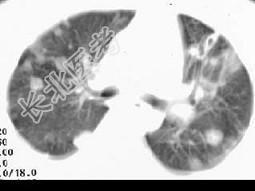

- 单项选择题女,32岁, 鼻梁双颊部出现红斑伴发热咳嗽2周,肘腕关节游走性疼痛, 结合CT图像,最可能的诊断为 ( )

D、SLE肺部浸润